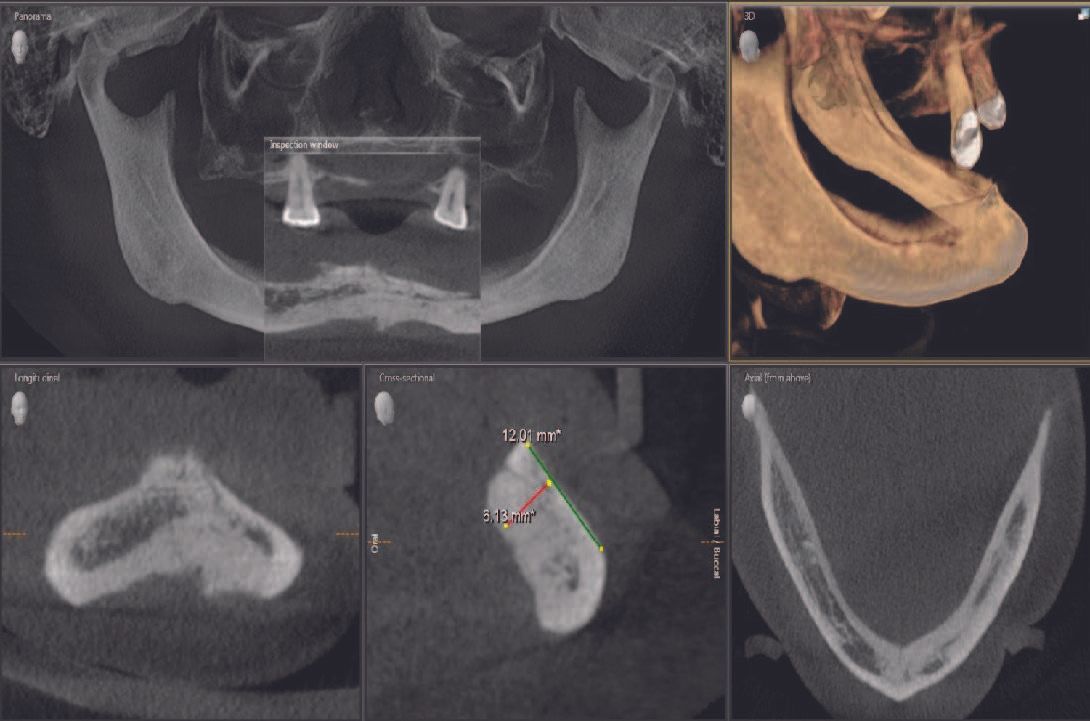

One of the greatest challenges that a restorative dentist can face is the rehabilitation of the edentulous mandible. When all teeth are removed, the mandible experiences resorption that is much more rapid and significant than the maxilla. The lack of a broad palatal surface, the muscle attachments on the mandible, and the mandibular movement make it even more challenging for the patient to comfortably wear and function with a conventional mandibular denture.

Oral rehabilitation with dental implants leads to better masticatory function in edentulous patients and there is a coincidence between patient perception and real improvement on masticatory function. It should be a primary goal for a dentist to treat complete mandibular edentulism with implant-supported overdentures.